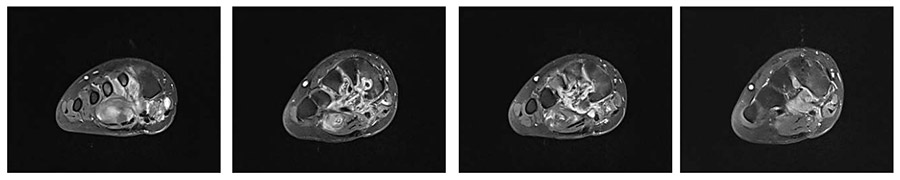

Ameliyat Öncesi: MR’da ayak orta ve medial ağırlıklı düzensiz sınırlı yaygın heterojen yumuşak doku kitlesi görülmekte